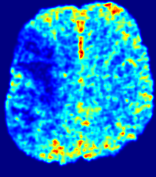

TimeSlice(i)(ii)(iii)(iv)(v)(vi)Refer to caption00555101010151515202020252525Refer to caption(a)(b)Refer to captionRefer to captionRefer to captionRefer to captionRefer to captionRefer to captionRefer to captionRefer to captionRefer to captionRefer to captionRefer to captionRefer to captionRefer to captionRefer to captionRefer to captionRefer to captionRefer to captionRefer to caption(a)(b)Refer to captionRefer to captionRefer to captionRefer to captionRefer to captionRefer to captionRefer to captionRefer to captionRefer to captionRefer to captionRefer to captionRefer to captionRefer to captionRefer to captionRefer to captionRefer to captionRefer to captionRefer to caption(a)(b)Refer to captionRefer to captionRefer to captionRefer to captionRefer to captionRefer to captionRefer to captionRefer to captionRefer to captionRefer to captionRefer to captionRefer to captionRefer to captionRefer to captionRefer to captionRefer to captionRefer to captionRefer to caption(a)(b)Refer to captionRefer to captionRefer to captionRefer to captionRefer to captionRefer to captionRefer to captionRefer to captionRefer to captionRefer to captionRefer to captionRefer to captionRefer to captionRefer to captionRefer to captionRefer to captionRefer to captionRefer to caption(a)(b)Refer to captionRefer to captionRefer to captionRefer to captionRefer to captionRefer to captionRefer to captionRefer to captionRefer to captionRefer to captionRefer to captionRefer to captionRefer to captionRefer to captionRefer to captionRefer to captionRefer to captionRefer to caption(a)(b)Refer to captionRefer to captionRefer to captionRefer to captionRefer to captionRefer to captionRefer to captionRefer to captionRefer to captionRefer to captionRefer to captionRefer to captionRefer to captionRefer to captionRefer to captionRefer to captionRefer to captionRefer to caption

Figure 6: Predicted concentration time series for the same patient shown in Fig. 4, where (i)-(vi) correspond to slices #1-6 respectively. Each grouped row displays (a) the measured concentration image sequences and (b) the predicted concentrations at corresponding time points.

3.2 Predicted CA Concentration

To better illustrate the prediction accuracy, and therefore the estimation accuracy of 𝐕𝐕{\bf V} and D𝐷{D}, of PIANO, we provide the corresponding predicted time-series of CA concentration images in Fig. 5 and Fig. 6 for the same patients in Fig. 3 and Fig. 4, respectively. We see that PIANO is capable of predicting the CA concentration given their initial state, indicating its ability to successfully capture 𝐕𝐕{\bf V} and D𝐷{D}. Note that although the concentration values for these two patients differ considerably, caused by the different total volume of injected CA, PIANO is still able to provide plausible estimates.